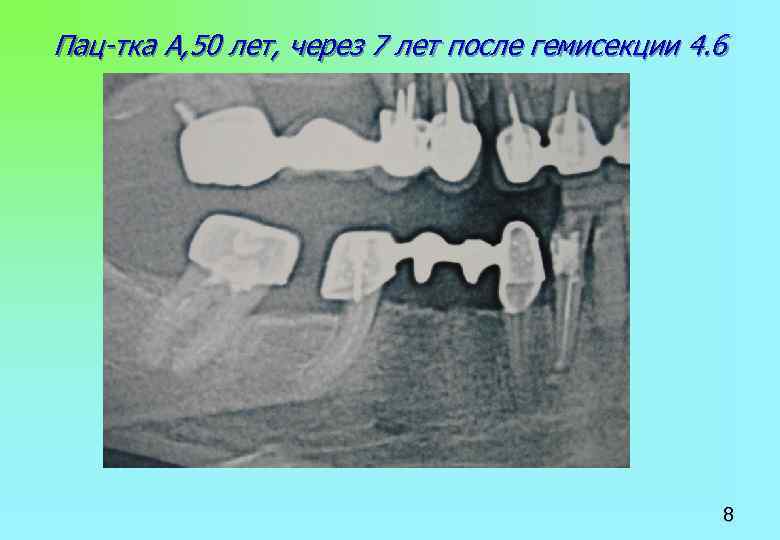

Пац-тка А, 50 лет, через 7 лет после гемисекции 4. 6 8 Пац-тка А, 50 лет, через 7 лет после гемисекции 4. 6 8